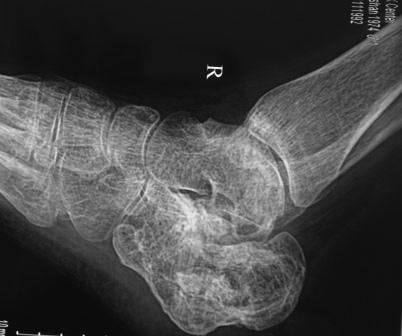

Вчера госпитализирован пациент 1970г.р., в ноябре 2014г, получил

о/перелом пяточной кости. в другой клинике произведена КДО аппаратом

Илизарова, после трех месяцев аппарат сняли, и больной начал наступать и

ходить, все это со слов больного (р-снимков нет.). Жалобы боль при

ходьбе, которая в динамике усиливается, об-но: деформация пяточной

кости, движение в г/стопном суставе почти в полном объеме, по медиальной

поверхности пятки рубец, плотно спаянный с костью.

Предварительный план: корригируюшая остеотомия пяточной кости, для

создания свода стопы (сможем ли опустить бугор пяточной кости из-за

натяжения ахиллово сухожилия), и подтаранный артродез.